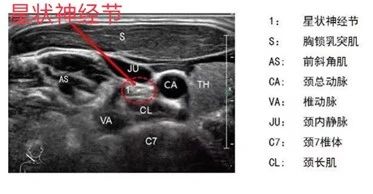

星状神经节阻滞术是在超声实时、精准的引导下,通过穿刺针将局麻药注射在星状神经节周围,从而阻滞支配头、面、颈、肩胛、上肢、前胸及后背等部位的颈交感神经,以调节交感神经系统张力,降低交感兴奋性。反复阻滞能够有效恢复交感-迷走平衡,改善失眠、焦虑、疼痛等一系列症状。

超声引导下可清晰显示星状神经节的位置及包绕星状神经节周围的神经、血管、气管等危险结构,引导穿刺针精确直达星状神经节周围(穿刺针极细,患者全程几乎没有痛感),创伤小、定位精确、安全性高、疗效显著,是一项高效、实用的微创技术。